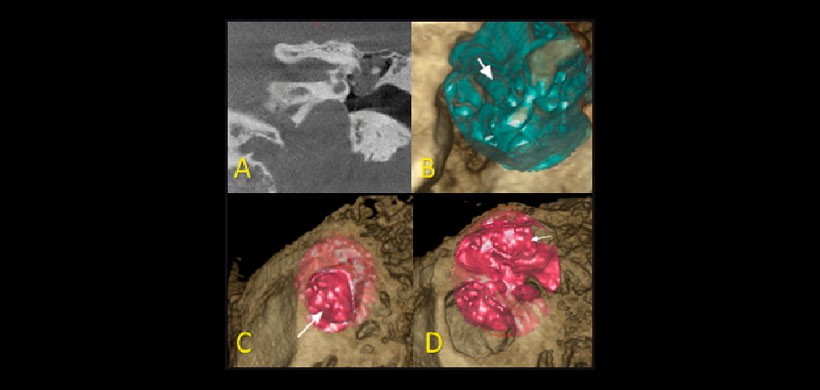

Figura 4: Colesteatoma ático-antromastoideo. A: vista coronal; B: ausencia pared lateral, segmento timpánico VII par; C: reconstrucción 3D algoritmo partes blandas, otoscopía virtual; D: ocupación del antro mastoideo.